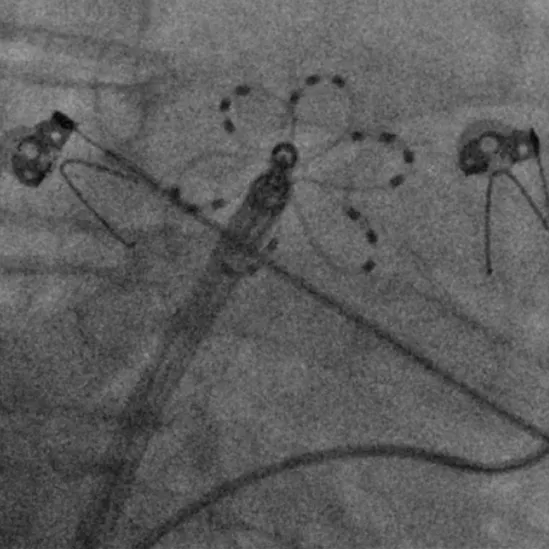

手术过程

手术在全麻下进行,消融策略涵盖双侧肺静脉、左房后壁及上腔静脉,总计消融73个位点,累计消融时间仅146秒。术中活化凝血时间(ACT)维持在250-300秒,未出现并发症。消融结束后,患者仍为房颤心律,经电复律成功转为窦性心律,手术顺利完成。

六瓣花导管呈网篮及花瓣形态放电